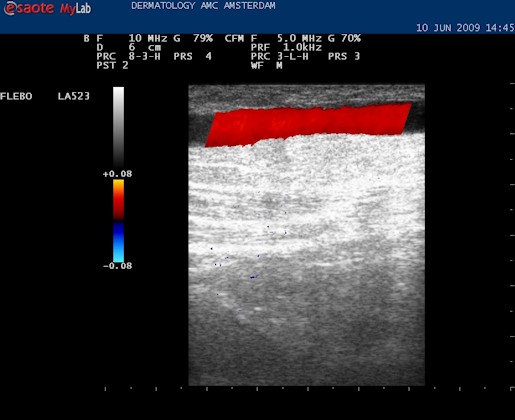

| Knijp in het been onder de echo kop. Het bloed stroomt omhoog en dat geeft een blauwe kleur (normaal) maar bij het loslaten stroomt het bloed terug en wordt het gehele vat langdurig rood. Nu weten we dat de kleppen in deze vene kapot zijn. De kleuren blauw (omhoog stromend, veneus) en rood (omlaag stromend) worden alleen goed weergegeven als de echokop goed wordt gehouden, met het pijltje omhoog. |

| Knijpen in het been: het vat wordt geheel rood bij loslaten: de vena saphena magna is insufficiënt. |